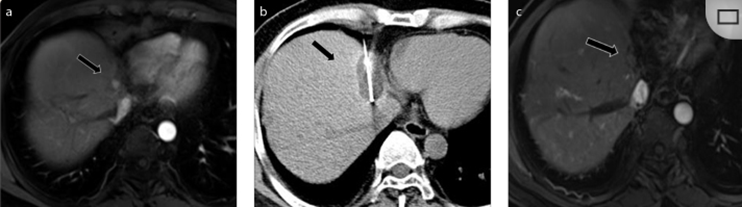

CT引導的冷凍消融

(c) 19個月后隨訪,沒有發(fā)生局部腫瘤進展。完全消融率為97%(66/68);2名患者均接受了額外的冷凍消融,隨后實現(xiàn)完全消融。平均隨訪期為 12.8 個月(范圍:3-27 個月)。所有患者均接受影像復查(CT 或 MRI)。11個病灶(16.2%)檢測到局部腫瘤進展,6、12和18個月時的累積局部腫瘤進展率分別為4%、8.2%和20.5%。8例出現(xiàn)遠處肝內(nèi)或肝外病變的患者接受經(jīng)動脈化療栓塞、經(jīng)動脈化療栓塞加射頻消融治療或全身化療。

(a)軸向CT顯示病變位置毗鄰心臟和上腔靜脈(黑色箭頭)。1個月后的軸向(e)和冠狀位(f)增強CT掃描顯示低密度區(qū)域,由于肉芽組織反應引起的邊緣增強。